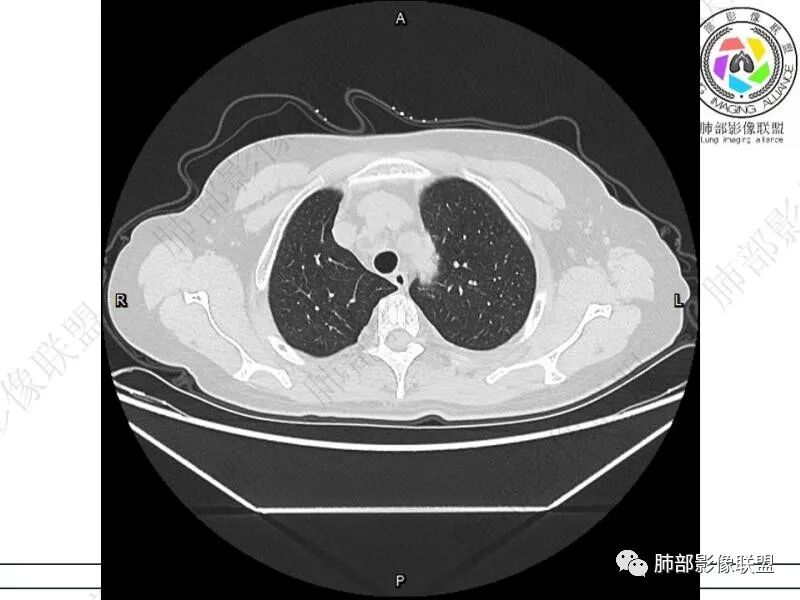

摘星空竹子:两肺胸膜下多发实性结节、磨玻璃影及实变影,短期复查病变有所进展,考虑感染性病变,隐球菌可能,患者有右半结肠癌手术史,转移不能除外。

简单:双肺及胸膜下多发小结节,双下肺胸膜下宽基底团块影,短期内病灶进展考虑炎性病变,隐球?患者ca术后,双肺小结节随诊除外转移

丽:双肺下叶胸膜下多发片状高密度影,边缘模糊不清,内可见支气管穿行,病变长轴平行于胸膜,考虑感染性病变,隐球菌

媛:肠癌术后,免疫力低下。两肺胸膜下结节及实变影,实变影长轴平行于胸膜,密度均匀,边界偏清,周围有晕征,短期复查进展,虽隐球菌荚膜抗原检测阴性,还是考虑隐球菌,鉴别OP

老年女性,结肠癌术后。两下肺胸膜下为主片状实变,右下肺短期复查融合且病灶长轴平行于胸膜,实变内可见支气管充气征,边缘磨玻璃晕,另两肺内胸膜下散在数枚小结节状、楔形实性灶。考虑感染性病变,隐球菌可能,鉴别肺转移。

2.影像特征:双肺胸膜下多发实性结节、磨玻璃影及实变影,胸膜下优势分布、晕征、胸膜下脂肪间隙存在,部分病灶边界平直征,有侧向融合趋势。